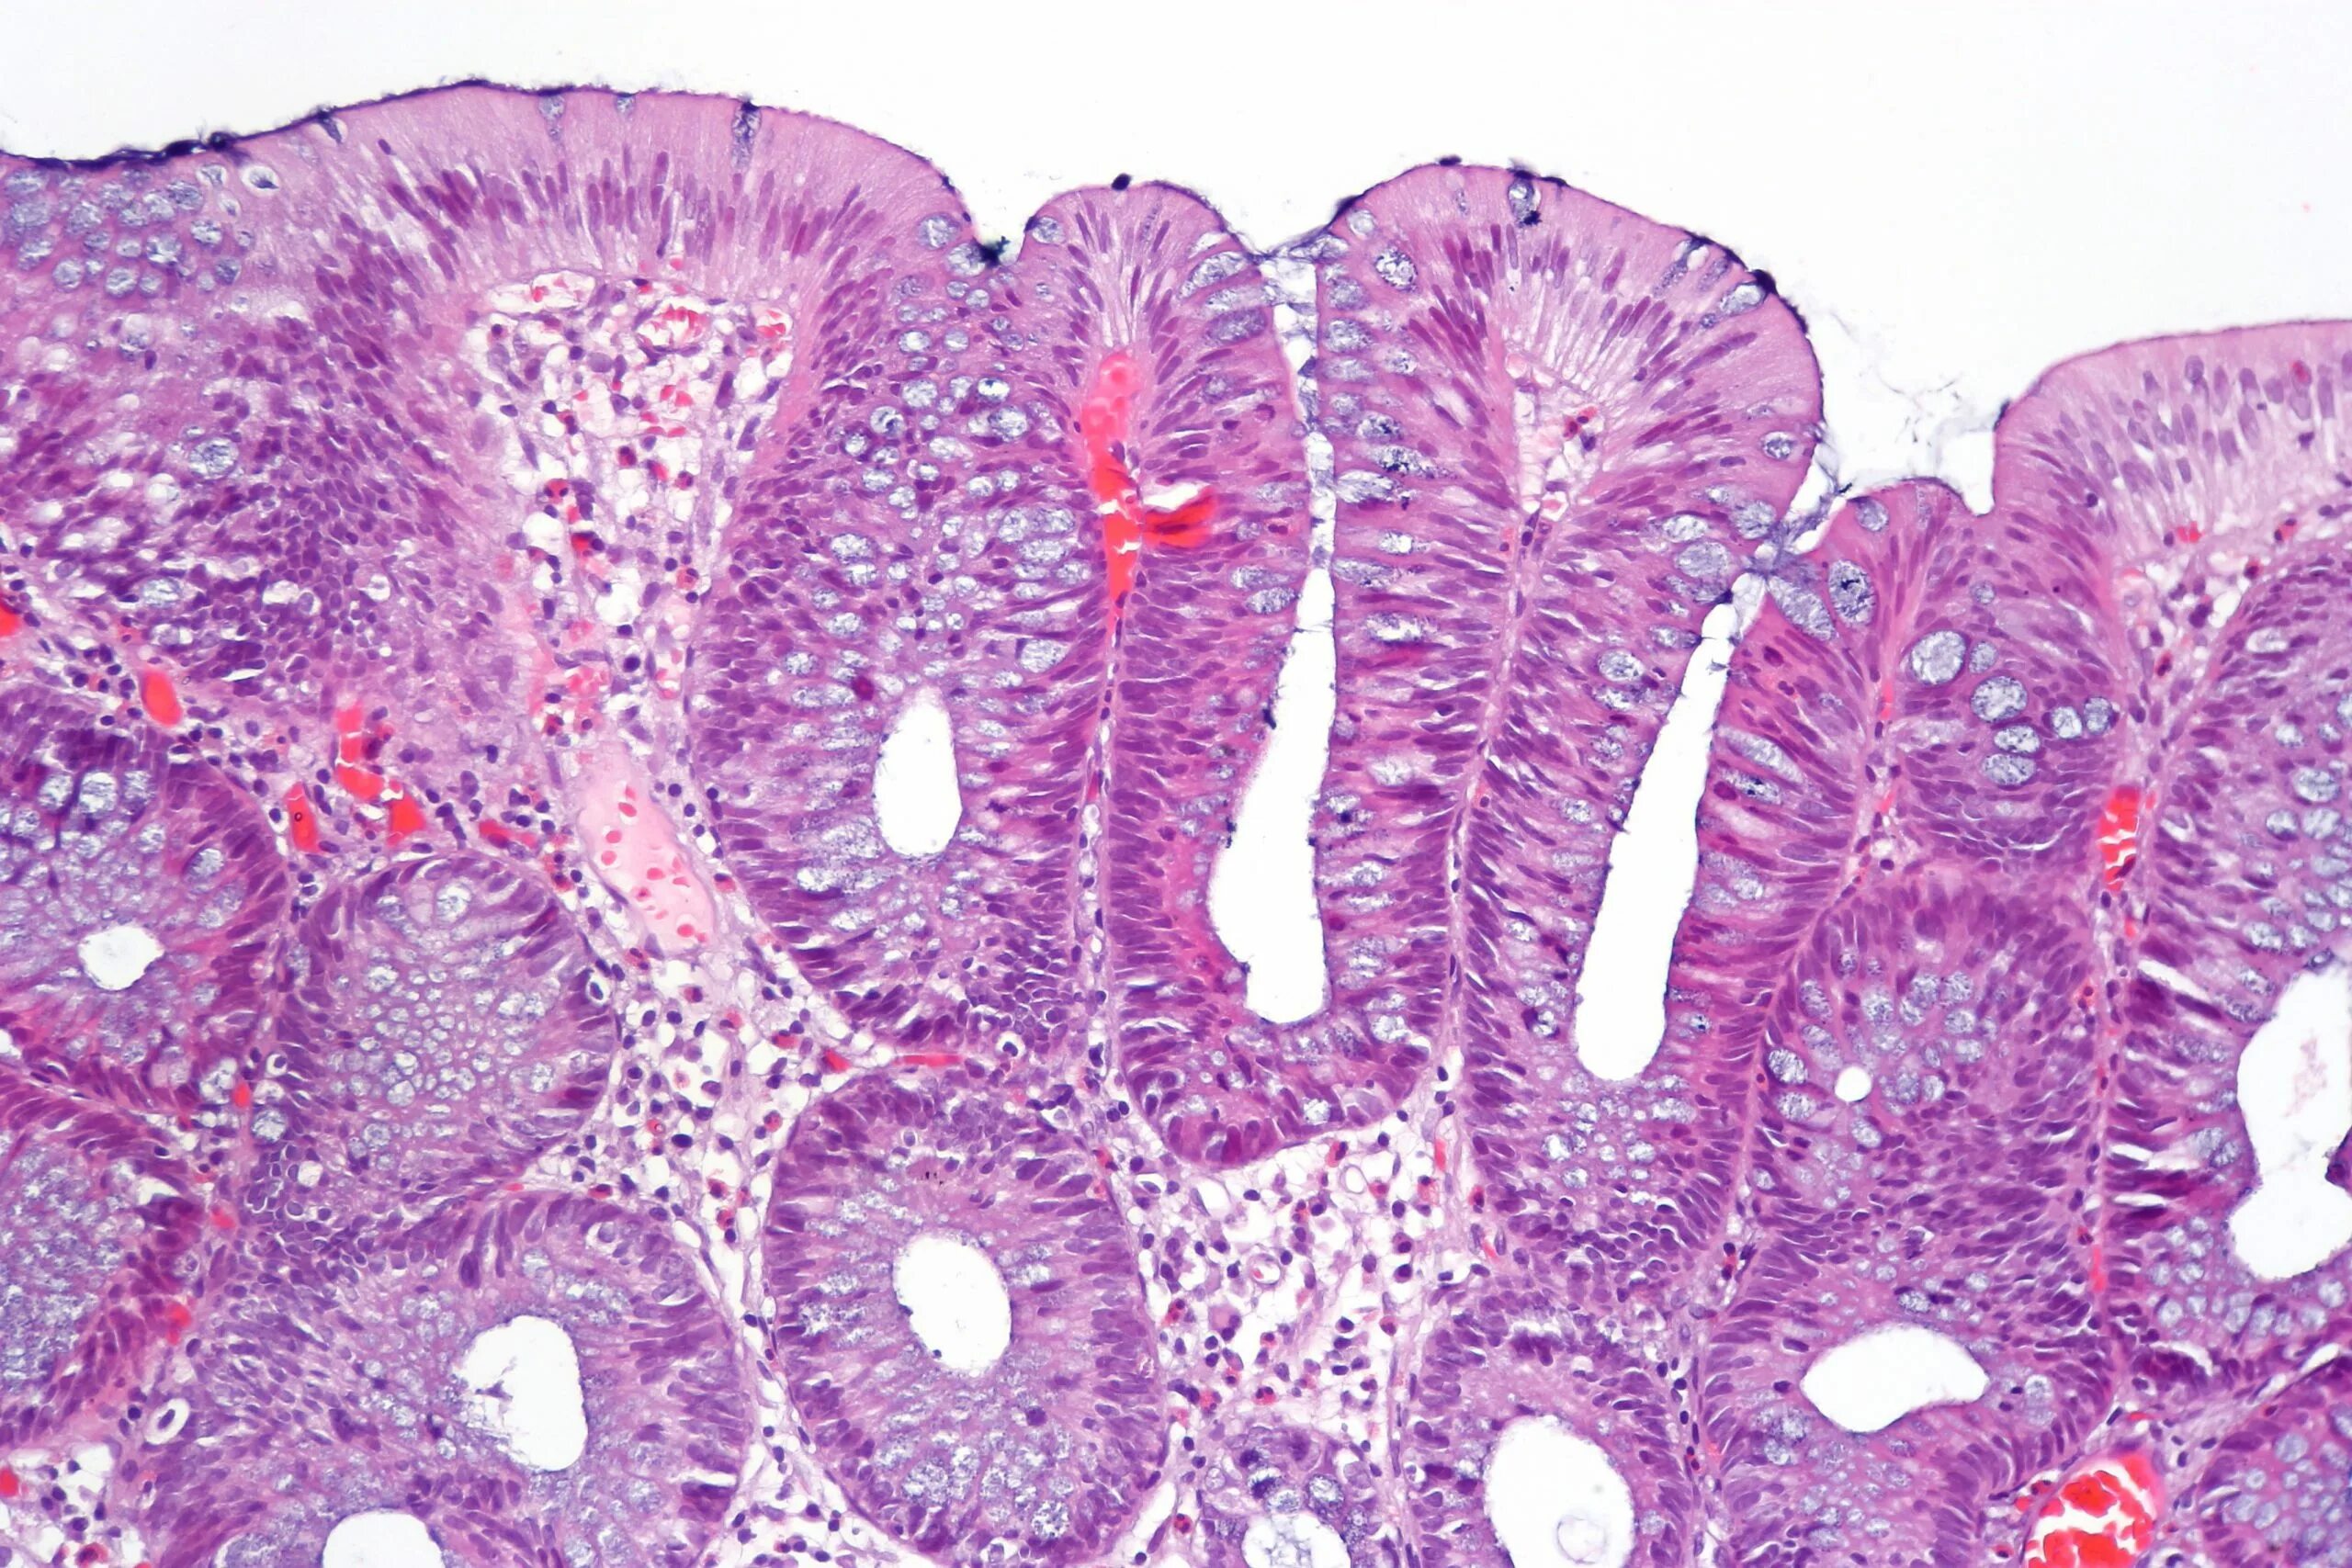

Полип желудка гистология